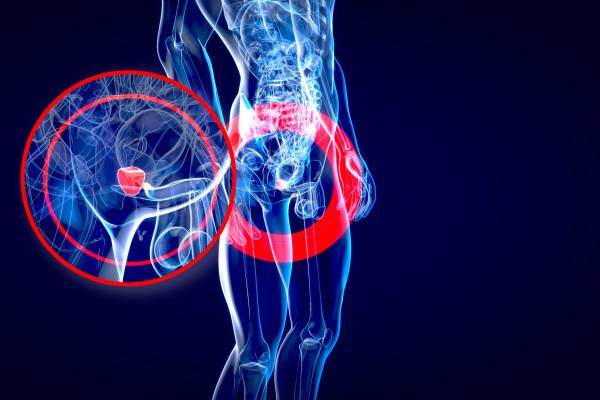

A cirurgia prostática é um procedimento crucial para tratar diversas condições da próstata, incluindo hiperplasia benigna da próstata (HBP) e câncer de próstata. O Dr. Marcelo Mai Jurado, urologista em Sorocaba, oferece tratamentos avançados para melhorar a saúde prostática dos seus pacientes. Neste artigo, abordaremos os tipos de cirurgias prostáticas, seus benefícios e o processo de recuperação.

A cirurgia prostática envolve a remoção total ou parcial da próstata ou de tecido prostático para tratar condições como HBP e câncer de próstata. Existem várias técnicas cirúrgicas disponíveis, dependendo da condição e do estado de saúde do paciente.

A cirurgia é indicada para pacientes com HBP que não respondem a tratamentos conservadores, obstrução urinária severa, ou para o tratamento do câncer de próstata localizado.